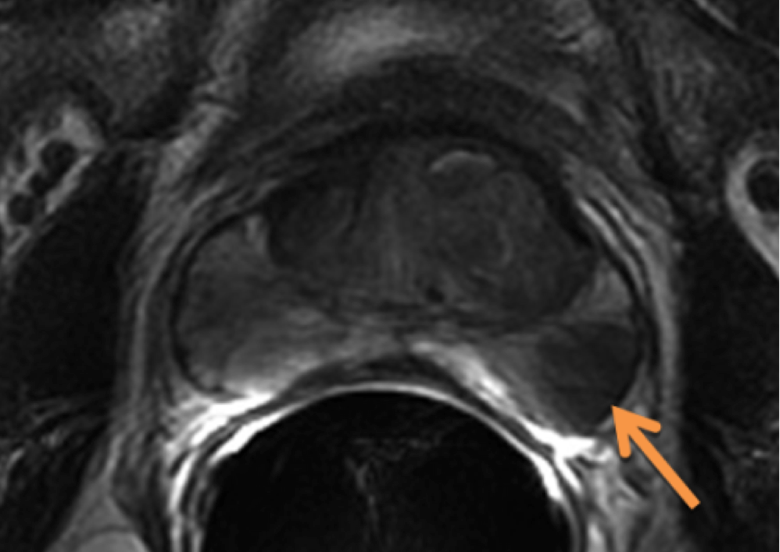

Additional imaging studies include an MRI of the prostate, generally with endorectal coil. If the PSA is > 20 then a bone scan is reasonable. A transrectal ultrasound is an intrinsic part of the biopsy in recent years. Peripheral zone cancers can be seen on the ulltrasound with hyper-echoic lesions in 69% of the cases. CT of the pelvis and prostate are used in radiotherapy treatment planning. Discrepancies between CT and MRI on fused images may exist (Roach):

There is significant variation of contours and techniques. The apex and base are regions most susceptable to variation. 3D perspectives help signficantly reduce this variation using transverse, sagital and coronal projections to determine the true extent of the prostate. More recently contouring atlases have been developed by the RTOG with grant assistance from the NCI and are available here. The following images are obtained from the RTOG contour atlases as an excerpt demonstrating areas of potential uncertainty.